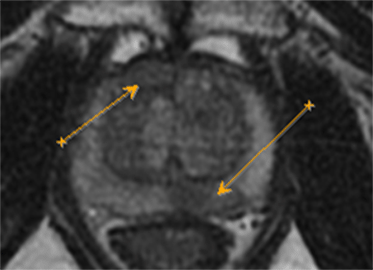

Существующие стандартные методы диагностики злокачественных опухолей предстательной железы обладают высокой точностью при выявлении заболевания. В РНПЦ ОМР им.Н.Н.Александрова используются и новые методы исследования, позволяющие улучшить стандартный подход на основе применения трансректального ультразвукового исследования с эластографией сдвиговой волны, которая открыла новые возможности количественной оценки жесткости ткани и позволяет определить локализацию подозрительных очагов.

Для подтверждения или исключения наличия злокачественной опухоли предстательной железы выполняется биопсия под контролем трансректального ультразвукового исследования. Она состоит из целевого этапа получения материала из подозрительных очагов, которые выявлены при помощи мультипараметрической МРТ таза и трансректального УЗИ с эластографией сдвиговой волны (т.к. точность определения диагноза возрастает, когда биопсия ориентирована на более жесткие области) и рекомендуется в сочетании с систематическим многоточечным этапом по определенной схеме.

Эластография показывает преимущества при выявлении в области верхушки и средней части простаты, тогда как МРТ – в визуализации базальной и переходной зон.

На рисунке представлен клинический пример пациента с повышенным уровнем ПСА. Ему выполнены мультипараметическая МРТ и трансректальное УЗИ с эластографией сдвиговой волны по данным которых определялись подозрительные очаги (указано стрелками или красным цветом). В последующем выполнена биопсии предстательной железы, которая состояла из систематического и целевого этапов. По результатам биопсии установлен диагноз рак предстательной железы с суммой баллов Глисона 4+3 (ISUP Grade 3). Пациенту выполнена радикальная простатэктомия в результатах которой подтвердилась правильно установленная стадия и лечение проведено успешно.

Установившийся тренд на изменение подходов к методике выполнения биопсии предстательной железы с включением целевого этапа при проведении систематической биопсии является результатом определенных успехов развития методов лучевой диагностики, в частности совместного использования при планировании биопсии результатов мультипараметрической МРТ и трансректального УЗИ с эластографией сдвиговой волны.